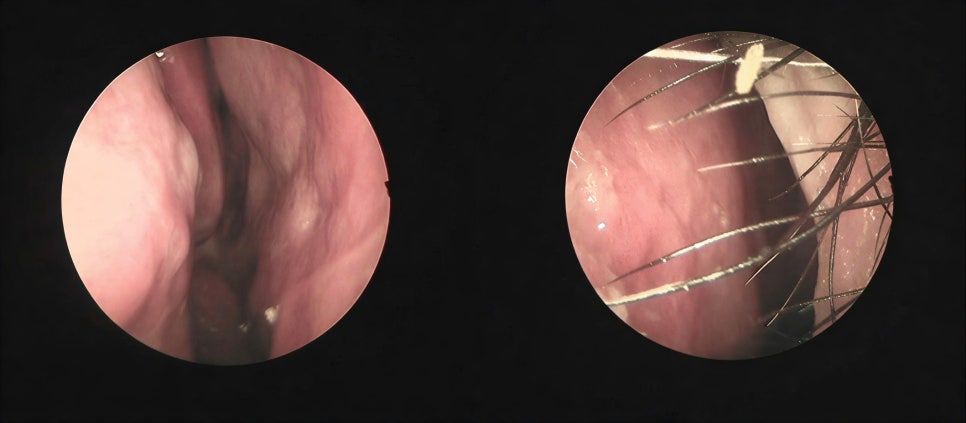

Trussed Structure Using ‘LOCK’ Technique for Septal Reconstruction in Contracted Nose Septal reconstruction is a crucial procedure in correcting a

Short Nose Correction: A Comprehensive Guide Short nose, also known as hypoplastic nose, is a common aesthetic concern among individuals